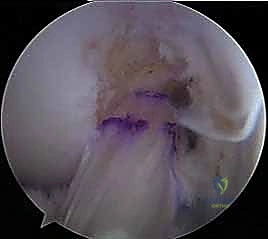

5. تمرير وتثبيت الحزم (Graft Passage & Fixation)

- يتم سحب حزمة (AM) عبر نفقها المخصص وتثبيتها في عظم الفخذ باستخدام أزرار تعليق معدنية صغيرة (Suspensory Fixation).

- يتم سحب حزمة (PL) عبر نفقها وتثبيتها بنفس الطريقة.

- اللحظة الحاسمة (تطبيق التوتر الديناميكي): لا يتم تثبيت الأوتار في عظم الساق عشوائياً. يقوم الدكتور هطيف بشد وتثبيت حزمة (AM) بينما الركبة مثنية بزاوية تتراوح بين 45 إلى 60 درجة. ثم يقوم بشد وتثبيت حزمة (PL) بينما الركبة في حالة تمدد شبه كامل (زاوية 10-15 درجة). هذه الخطوة العبقرية هي التي تعيد الميكانيكا الحيوية الطبيعية للركبة. يتم التثبيت النهائي في الساق باستخدام براغي تداخلية قابلة للامتصاص (Bio-absorbable Screws).